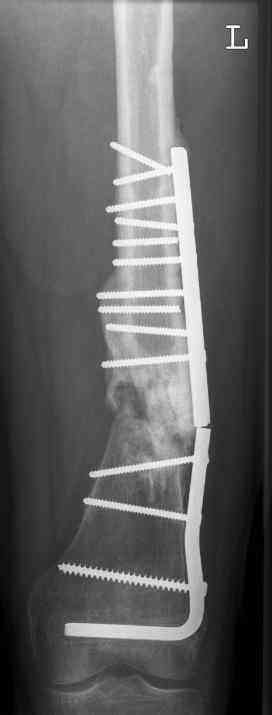

july 05: LISS femur, LCP plate tibia, double recon. plate post. acetabulum

oct 05: cancellous bone graft femur

aug 06: blade plate + bone graft

nov 06: revision blade plate

feb 07: retrograde nail + bone graft + BMP

may 07: dynamisation nail

sept 07: locking screw removal (max. dynamisation reached)

nov 07: persistant non-union distal femur; other fractures healed

uneventfully.